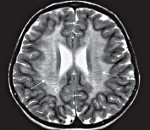

С целью диагностики вида метаболической аномалии проводится целый ряд биохимических тестов с определением уровня ферментов и накапливающихся метаболитов. Очаги демиелинизации хорошо визуализируются при помощи МРТ, могут быть обнаружены и на КТ головного мозга. Обычно демиелинизация видна на МРТ головного мозга еще до клинической манифестации лейкодистрофии. Благодаря развитию генетики, лейкодистрофия имеет разработанную ДНК-диагностику, а отдельные ее формы (метахроматическая, адренолейкодистрофия, глобоидно-клеточная) - возможность пренатального диагностирования.